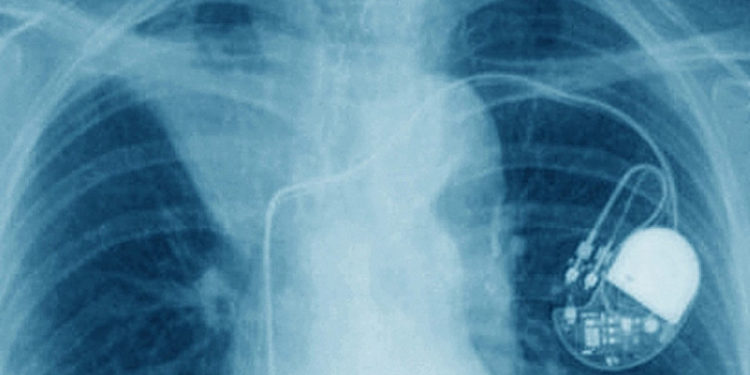

Нескольких врачей из уездной больницы Ясс подозреваются в проведении незаконных хирургических вмешательств. У следователей есть информация, связанная с десятками операций, в ходе которых дефибрилляторы и кардиостимуляторы удалялись у умерших пациентов, а затем устанавливались другим пациентам.

Все устройства были одноразовыми и не должны были использоваться повторно.